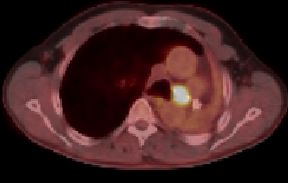

| PET-CT | 60jähriger Mann 18 Monate nach Pneumektomie links wegen Plattenepithelkarzinom des linken Lungenoberlappens pT2a pNo Mo![]() ![]() |